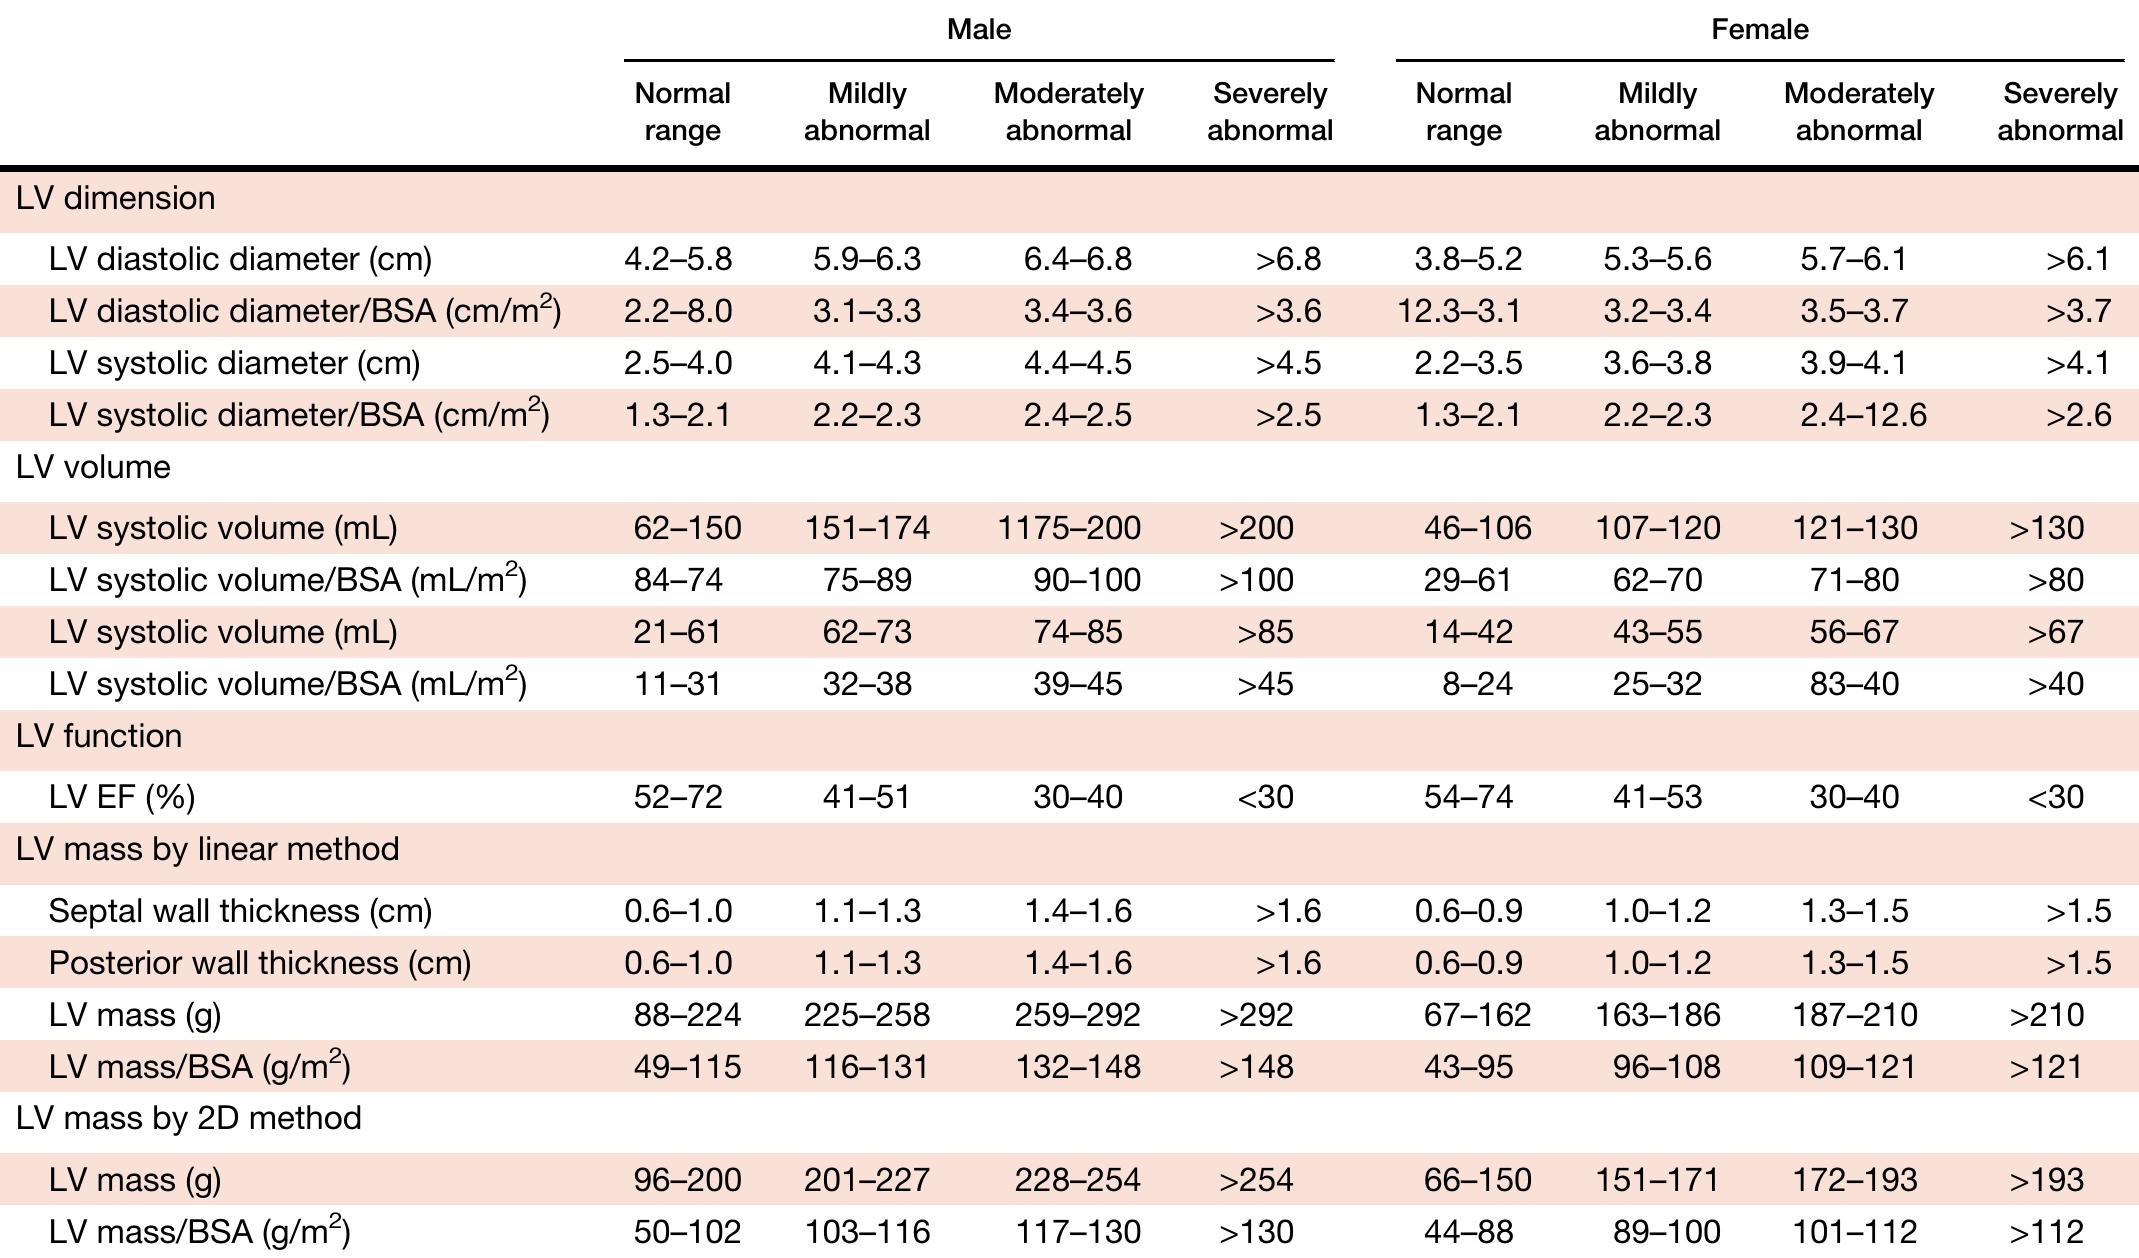

The rapid technological developments of the past decade and the changes in echocardiographic practice brought about by these developments have resulted in the need for updated recommendations to the previously published guidelines for... more